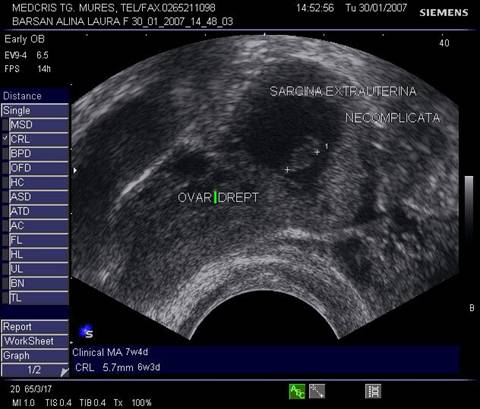

Fig nr 52

Langa ovarul drept ( cu sageata lunga ) se observa o formatiune ovalara cu ecou

hipoecogen central, sarcina extrauterina la 5 sapt. si 3 zile de amenoree ( doua sageti )

Fig nr 53 Aceeasi sarcina extrauterina ca in figura precedenta, se evidentiaza coroana trofoblastica la ecoul doppler color si se schiteaza vezicula vitelina ( cu sageata )